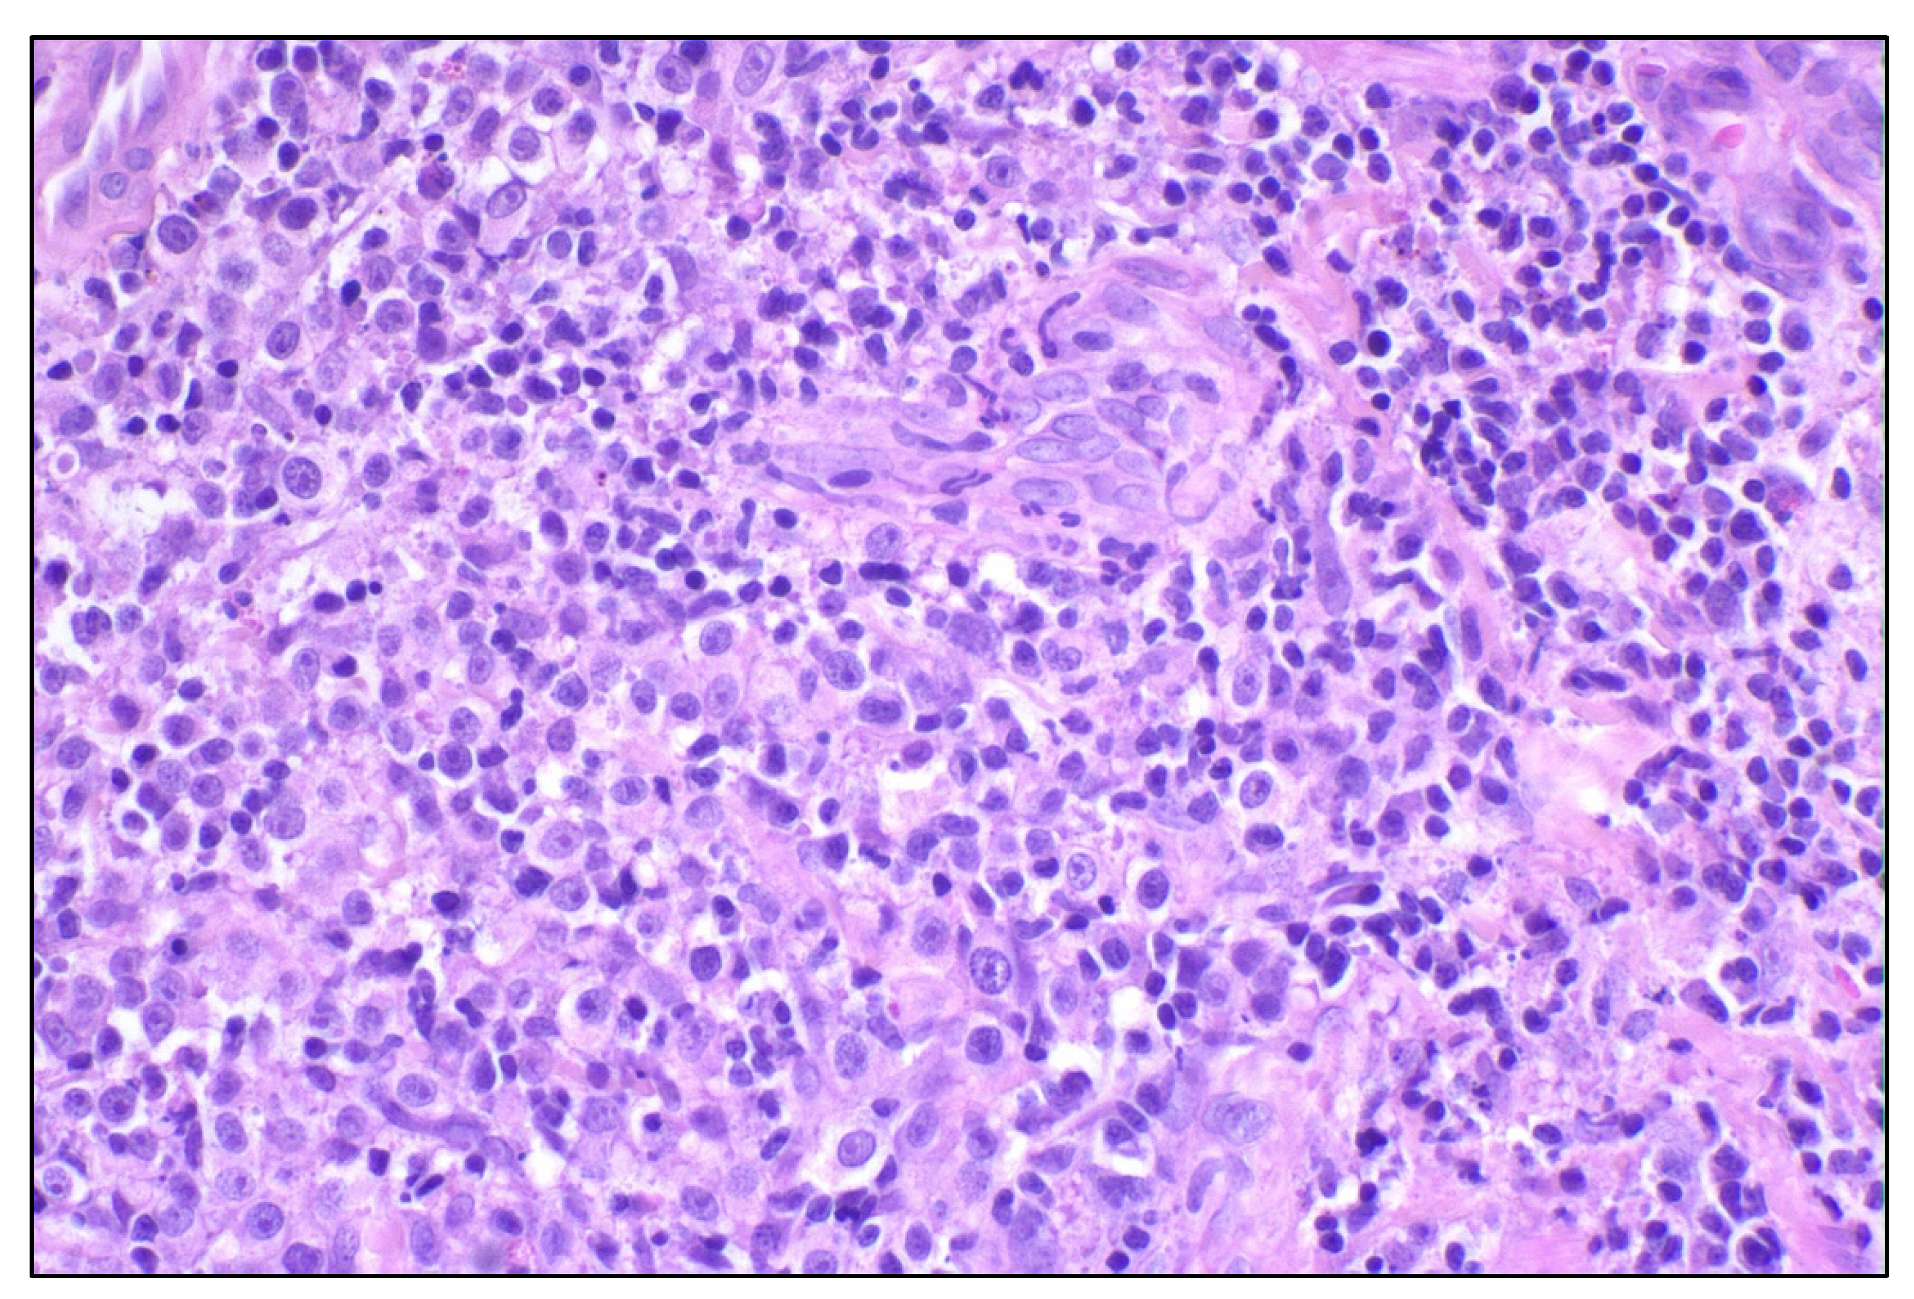

- Lenz, J.A.; Assenmacher, C.-A.; Costa, V.; Louka, K.; Rau, S.; Keuler, N.S.; Zhang, P.J.; Maki, R.G.; Durham, A.C.; Radaelli, E.; et al. Increased Tumor-Infiltrating Lymphocyte Density Is Associated with Favorable Outcomes in a Comparative Study of Canine Histiocytic Sarcoma. Cancer Immunol. Immunother. 2021, 71, 807–818. [Google Scholar] [CrossRef] [PubMed]